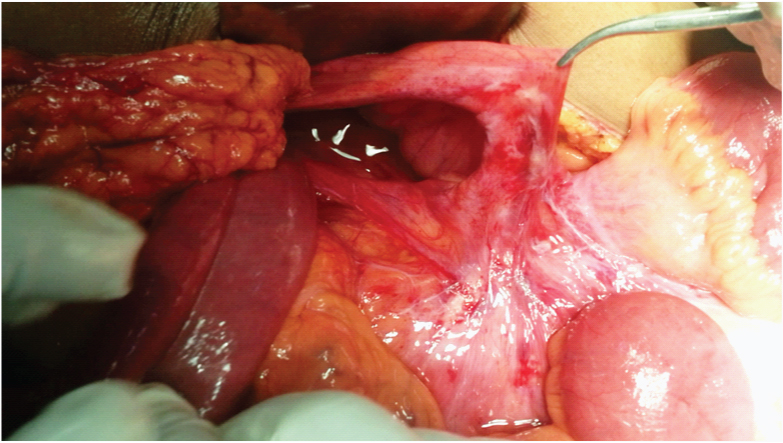

Case 2: Patient presented to our casualty with features of intestinal obstruction. He was febrile and dehydrated, tachycardia was present. Abdomen was distended, with diffuse tenderness, guarding and rebound tenderness. X ray abdomen showed multiple air fluid levels and dilated small bowel loops. He was posted for emergency exploratory laparotomy. During laparotomy ileum was found herniated in the left paraduodenal fossa with 50 cm of ileum found gangrenous within it and proximal segment dilated [Table/Fig-3,4]. The constriction band was formed by inferior mesenteric vein. The contents were reduced, gangrenous bowel was resected and an end to end ileo-ileal anastomosis was done in two layers. The defect was closed with peritoneum to the DJ flexure after preserving the inferior mesenteric vein. Postoperative period was uneventful and he was discharged on postoperative day 9.

Shows the dilated small bowel in the left paraduodenal fossa.

Shows the segment of the small bowel which was found gangrenous in the left paraduodenal hernia sac, which was later resected and an end to end ileo-ileal anastomosis was done.